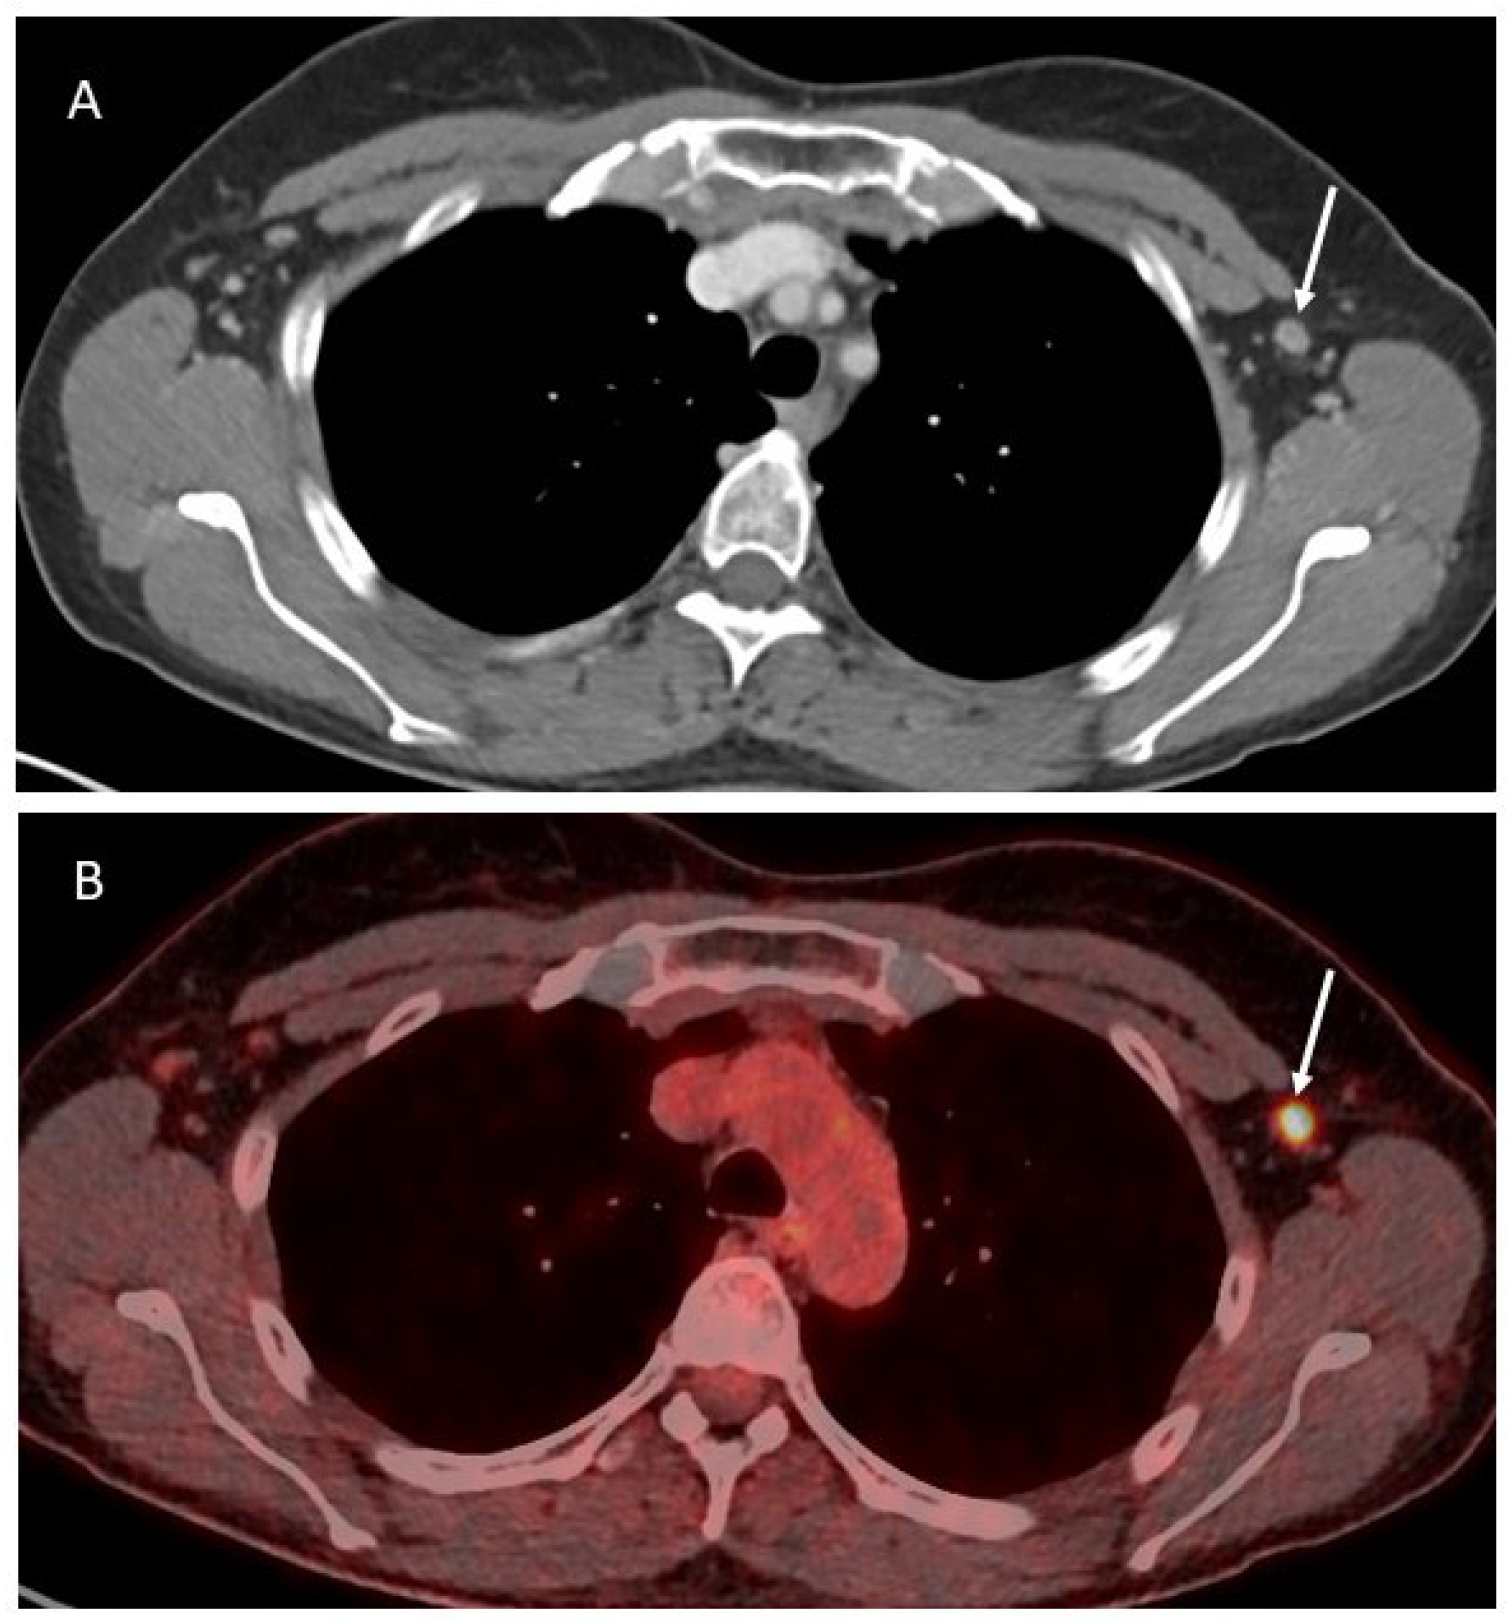

In OC patients, all the abovementioned imaging techniques are valid options to evaluate the presence of axillary lymphadenopathies (Figure 2).

Figure 2.

Axial contrast-enhanced CT image (A) showing a slightly enlarged lymph node in the left axilla (white arrow), corresponding to a pathologic activity on the PET-CT (B).

However, considering the relatively superficial location of these lymph nodes, an adjunctive unexpensive and widely available imaging option is ultrasound (US). The criteria for pathological nodes at US include the size, as well as the shape and the internal structure. The size itself tends to be of limited value [34]. Therefore, morphological criteria may be additionally evaluated. The normal node has a thin hypoechogenic cortex in the periphery and an echogenic hilus. If there is a pronounced fatty part in the center, this becomes hypoechogenic. Pathological nodes tend to become more rounded, indicated as loss of the oval-shape. Therefore, when the normal length to width ratio >2 decreases to <1.5 the presence of metastasis can be suspected. The compression of the hilus, and especially the absence of the hilus, is highly suggestive of malignancy [35]. The use of color Doppler to differentiate benign form malignant lymph nodes is debated, with some authors suggesting good performances [36], and others showing fewer specific results [7]. The presence of axillary lymphadenopathies in OC patients does not preclude the possibility of an optimal debulking but it has to be carefully considered before planning the treatment.